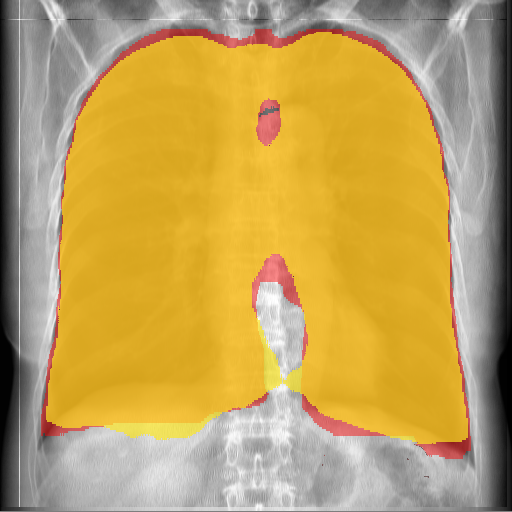

A total of 990 CT cases were used to create pairs of DRR and Lung mask for training the segmentation FCNN. Data was split in 80-20 training validation ratio. We threshold the continuous output of the segmentation network to get a binary segmentation prediction (threshold=0.95). An example result of the segmentation algorithm is given in Figure 6 . The Dice coefficient was chosen as the segmentation metric.On the training set the Dice score was 0.971 while on the validation set the Dice score was 0.953. Since our lung segmentation algorithm is used for normalization of the input to the extraction FCNN we were satisfied with the result. To the best of our knowledge, this is the first work that performs lung segmentation using CT ground truth. As a result, we were not able to perform a comparison to other works.

Refer to caption

(a)

(b)

Figure 6: (a) Original DRR (b) Segmentation Result (Red: GT Mask derived from CT, Yellow: Segmentation result, Orange: overlap)